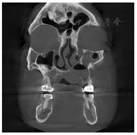

患者,男性,65岁,因反复发作上颌前牙区肿胀疼痛6年余。6年前出现上颌前牙区肿胀不适,开始时无明显疼痛,未治疗,2个月前再次发作,伴上前牙疼痛就诊,拍摄口腔CBCT发现上颌偏左侧大面积低密度影像,有不连续的骨间隔影,且累及左侧鼻底及鼻腔外侧壁(图1,图2,图3)。

口腔检查:口腔颌面部左右不对称,左侧鼻旁区明显隆起,按压乒乓球样感,双侧颞下颌关节无弹响,无压痛。口内见12-23前庭沟处膨隆,大小约4.2 cm×2.0 cm,边界清,质软,有轻微压痛,22-24腭侧球形膨隆,大小约1.5 cm×1.5 cm,边界清,质软,可触及波动感,无压痛。22唇侧有一瘘管,挤压有脓液溢出。鼻内镜检查:鼻腔黏膜略充血,左侧鼻底及下鼻道见明显隆起(图4),将左侧下鼻甲推向外上方,鼻中隔向右侧偏曲,左侧鼻道较宽敞,中鼻道略隆起,未见分泌物。CBCT示:12-24根尖区可见3.7 cm×1.6 cm大小的低密度影像,边界清楚,密度均匀,内见不完全的骨间隔影,肿物累及左侧鼻底及鼻腔外侧壁,左侧上颌窦内见液平面。